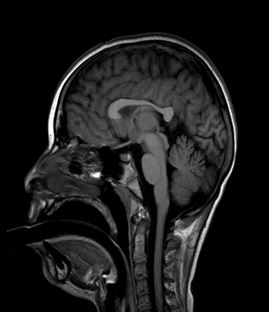

• Prueba de neuroimagen: RM cerebral normal (repetida en varias ocasiones)